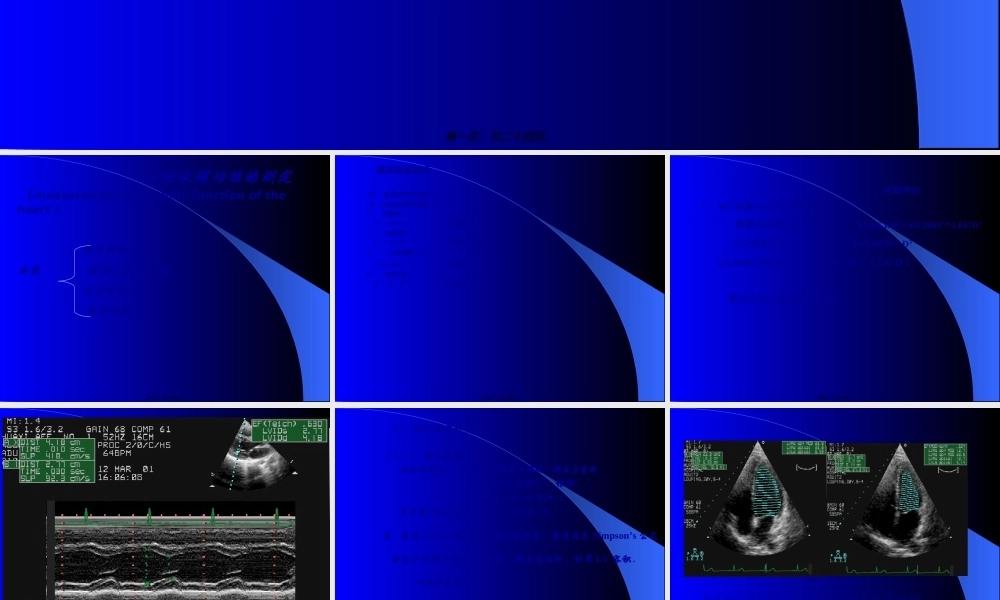

心脏功能(gōngnéng)的超声测量(UltrasonicMeasurementofCardiacFunction)曹礼庭第一页,共二十四页。心脏收缩功能的测定(measurementofsystolicfunctionoftheheart)流量指标内容时间(shíjiān)指标速度指标泵功能指标第二页,共二十四页。基本检查指标EDV(左室舒张期末容积,ml)ESV(左室收缩期末容积,ml)SV(每搏量)SV=EDV-ESV正常值60~130mlCO(心输出量)CO=SV×HR正常值3-6L/minCI(心脏指数(zhǐshù))CI=CO/BSA正常值2-3L/min/m2EF(射血分数)EF=SV/EDV正常值60~75%第三页,共二十四页。一、流量指标1、ME容量(róngliàng)计算法椭圆形体积法V=π/6.LD2=π/62DD2=1.047D3立方体积法V=1.047D3=D3Teichholtz校正公式V=7.0×D3/(2.4+D)据此可以计算出其它指标。第四页,共二十四页。第五页,共二十四页。2、2DE容量计算法(1)、单平面法面积长度法:取心尖二腔或四腔观,测出左室的面积A及长径L.根据:V=8A22/3πL=0.85A22/L/L单平面Simpson’s法:V=∑Ah⊿注:美国(měiɡuó)超声心动图协会推荐,应用改良Simpson’s公式,将两个长轴分为20个等份,将平面相加,计算LV容积.可推算其它指标.第六页,共二十四页。舒末左心室容积(róngjī)收末左心室容积(róngjī)第七页,共二十四页。陈旧(chénjiù)心梗,心尖部室壁瘤Simpson法测量左室容积第八页,共二十四页。(2)双平面法:取二尖瓣水平短轴观及心尖二腔或四腔观,测出二尖瓣水平短轴面积(miànjī)Am及左室长径L.根据:圆柱-圆锥体法:V=2Am.L/3圆柱体法:V=Am.L圆柱-半椭圆体法:V=5Am.L/6(3)三平面法(改良Simpson’s法/圆柱-截头圆锥-圆锥体法)V=Am.L/3+(Am+Ap)/2×L/3+1/3Ap.L/3Ap:乳头肌短轴左室的面积。第九页,共二十四页。3、Doppler计算(jìsuàn)法主动脉血流计算法SV=A•VTIA:Ao根部面积A=π/4D(ME/2DE测量)。VTI:AVO速度时间积分。二尖瓣血流计算法SV=A•VTIA:MVO面积。VTI:MVO舒张期速度时间积分。据此可推算:每分量CO=SV•HR(HR心率)每搏量CI=CO/BSA(BSA体表面积)第十页,共二十四页。第十一页,共二十四页。二、时间指标1、射血前期(qiánqī)(PEP):ECG的Q波----PDE上AV开放的时间。2、射血时间(LVET)ME上AV开放点----关闭点的时间。PDE上AV开放信号-----关闭信号的时间。3、PEP/LVET4、等容收缩时间ICTECG的R波-PDE上AV开放的时间减去ECG的R波-PDE上MV关闭的时间。5、总电机械收缩时间(TEMS)ECG的Q波----AV关闭点的时间。第十二...

1、当您付费下载文档后,您只拥有了使用权限,并不意味着购买了版权,文档只能用于自身使用,不得用于其他商业用途(如 [转卖]进行直接盈利或[编辑后售卖]进行间接盈利)。

2、本站所有内容均由合作方或网友上传,本站不对文档的完整性、权威性及其观点立场正确性做任何保证或承诺!文档内容仅供研究参考,付费前请自行鉴别。

3、如文档内容存在违规,或者侵犯商业秘密、侵犯著作权等,请点击“违规举报”。